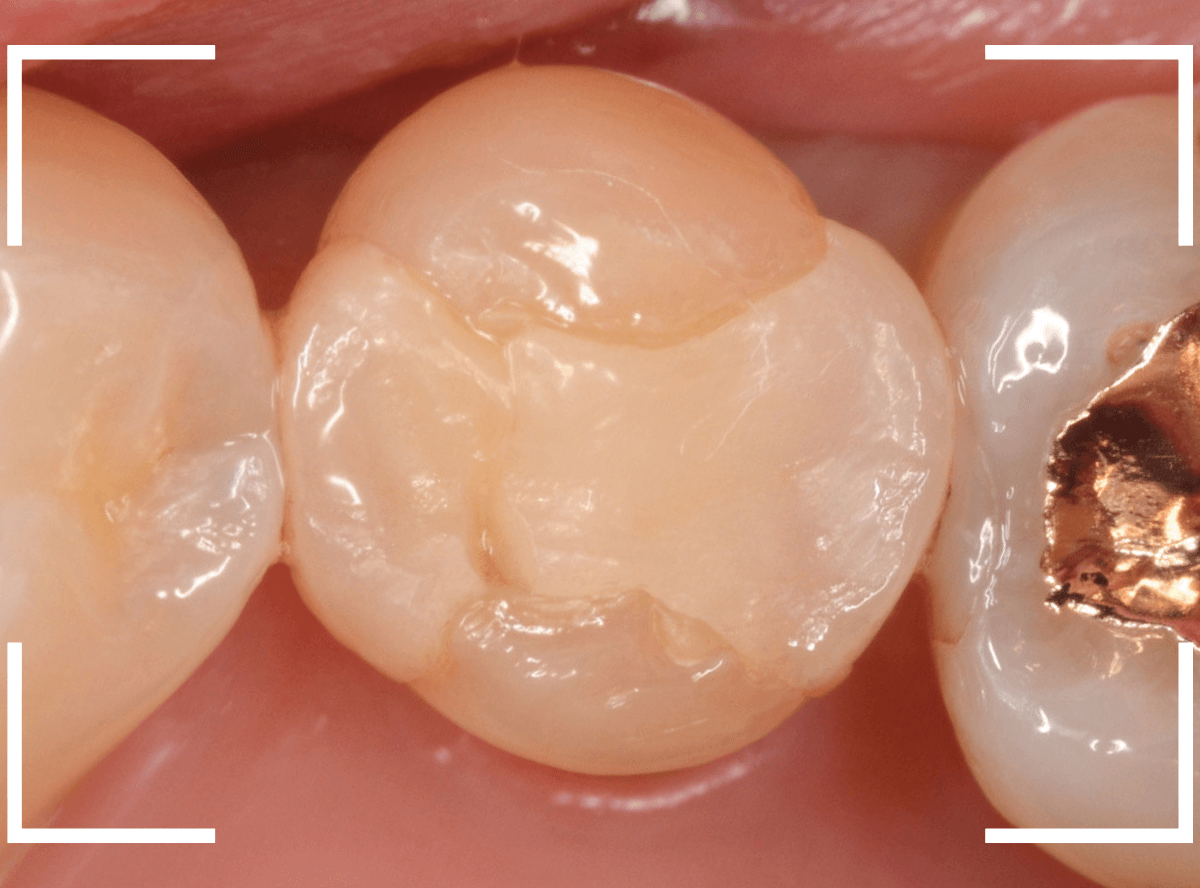

お口の中でsetしたところです。

なかなか手が届きづらい場所で、set処置も苦労しましたが、何とか自然な形で治療できたかと思います。

set後の写真です。

見た目にも違和感なく、患者さんにも満足していただけました。

E-MAXなどに比べ、色調再現性に劣るジルコニア・インレーですが、除去前と遜色ない審美性でsetできたかと思います。

大きな虫歯治療後ですが、set後も特に症状なく経過してる様子で、ホッとしました。

側面から見ても、自然な仕上がりになったかと思います。

今回も自然な見た目で治療できたと思います。

最終的なつめ物(E-MAX・インレー)をsetしたところです。

上から見ても、側面から見ても、患者さんに満足していただける仕上がりになりました。

こちらがset後の写真です。

今回は、元々の歯の色が濃かったため、セラミックとの色調の調和が難しかったです(><)

お口の中で合わせたところです。

今回も、うまくお口の中に合せる事が出来たかと思います。

最終的なset時の状態です。

今回も、自然な見た目で修復出来たかと思います。患者さんにも喜んでいただけました。

ほとんど調整なく、お口の中でぴったりと合わせる事ができました!

今回も、お口の中でうまく合わせられたかと思います。

(今回も、うまく周りの歯の明るさに合せる事が出来たかと思います。

E-MAXに比べて色合わせが難しいジルコニアですが、今回もE-MAXとあまり遜色ない状態で合わせる事が出来たかと思います。

今回も、なんとか周囲の歯と調和した形態・色調に仕上げられたと思います。

患者さんにも喜んでいただき、ホッとしました。

いかがでしょうか、E-MAXと並べてジルコニアもあまり遜色なく仕上げられたと思います。

調整も少なく、患者さんにも満足いただき、ホッとしました。

お口の中にセットし、調整直後の写真です。

以前、特にジルコニア・インレーはまわりの歯との色合わせに苦労した事が多かったですが、最近ではかなり周りの歯に近い色合いに合わせる事ができるようになっています。

こちらがE-MAXを装着後の写真です。

歯を削った部分との境界や、周りの歯と見た目の違和感なく仕上がったかと思います。

角度を変えて見ても、違和感ないかと思います。

このように、最近のセラミック素材は、かなり違和感のない仕上げができるようになりました。